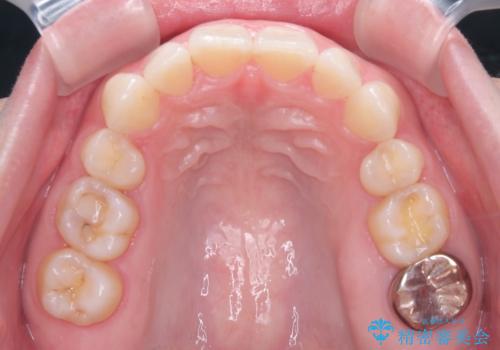

- 治療計画

- 患者様は、上下顎の歯列不正と前歯部の突出感を主訴としてご来院されました。診断の結果、上顎左右第一小臼歯を抜歯することでスペースを確保し、歯列全体を整える方針としました。本来はワイヤー矯正が推奨されるケースですが、患者様のご希望により、透明なマウスピース型矯正装置「インビザライン」を使用した治療計画を立案しました。治療期間は約3年で、奥歯の噛み合わせを維持しながら、徐々に前歯の位置を整えました。

インビザラインは見た目の目立ちにくさと取り外しが可能な点がメリットですが、複雑なケースでは治療計画の精密さが求められます。本症例では奥歯の噛み合わせが崩れないよう注意を払いながら、マウスピースの交換タイミングを細かく設定しました。患者様には装着時間を守っていただくことが重要で、1日20時間以上の装着が必須です。また、抜歯部位のスペースを閉じる過程で、歯の動きが停滞しやすい時期もあるため、定期的なチェックを通じて治療が順調に進むよう管理しました。